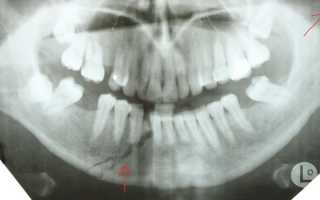

Диагностирование травмы

Перелом челюсти – это травма, которую можно заподозрить без использования специализированного оборудования. Однако для того, чтобы провести адекватное лечение и точно оценить степень повреждений, необходимо пройти детальное обследование у специалиста. После первичного осмотра врач назначит наиболее подходящие методы для выявления трещин. К примеру:

- рентгенографию;

- ортопантомографию;

- компьютерную томографию (КТ);

- магнитно-резонансную томографию (МРТ).